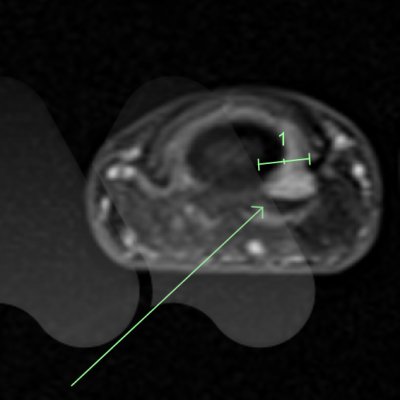

This is a rare benign (non-cancerous) growth often under the fingernail or fingertip pulp and can involve bone.

It commonly causes severe pain in the fingertip in cold environments and extreme pain and sensitivity to touch. X-Ray and MRI can be useful tests in confirming the diagnosis.